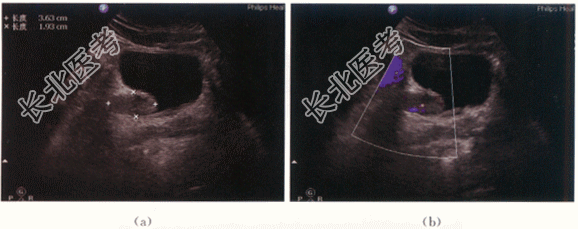

患者,男性,48岁,因“无痛性肉眼血尿半年”就诊。外院超声检查发现右侧输尿管轻度扩张积水,未行特殊诊治。

二、影像资料